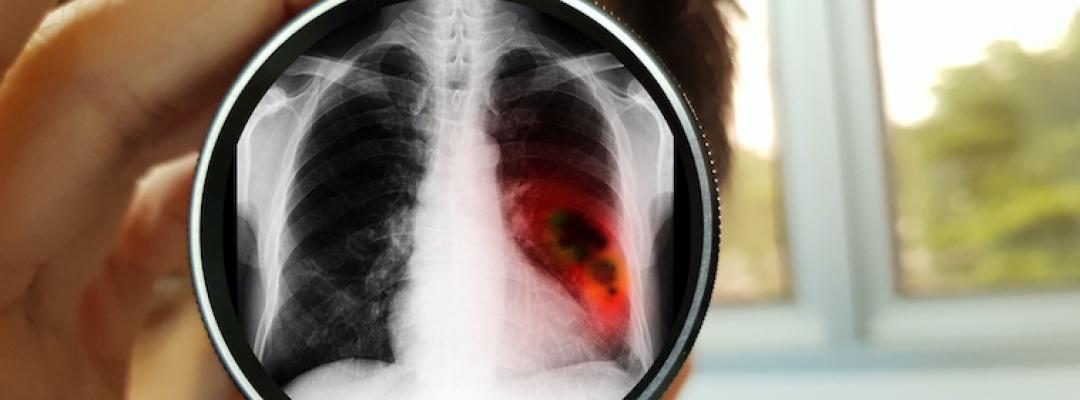

Besteht der Verdacht auf Lungenkrebs, kommen verschiedene Untersuchungen zur Anwendung: Lungenröntgen, Computertomografie vom Brustkorb und die Bronchoskopie sowie meist auch ein Laborbefund. Auf Basis einer Biopsie lässt sich dann die definitive Diagnose erstellen. Mit weiterführenden Untersuchungen wie jenen von Thoraxorganen (andere Lungenseite), Lymphknoten, Bauchhöhle (Leber, Nebennieren), Skelettsystem und auch Hirn mittels bildgebender Verfahren wird das Krebsstadiums bestimmt und die passende Therapie festgelegt.1 In der Lungenkrebstherapie wird mittels Operation versucht, das vom Krebs befallene Gewebe zu entfernen, ohne die Atemfunktion zu sehr einzuschränken. Vor und nach der Operation wird häufig auf Chemotherapie gesetzt, in vielen Fällen zusätzlich auf Strahlentherapie. Mit der neuen Immuntherapie können bei nicht kleinzelligem Lungenkarzinom unter Umständen Tumorrückbildungen erreicht werden.1